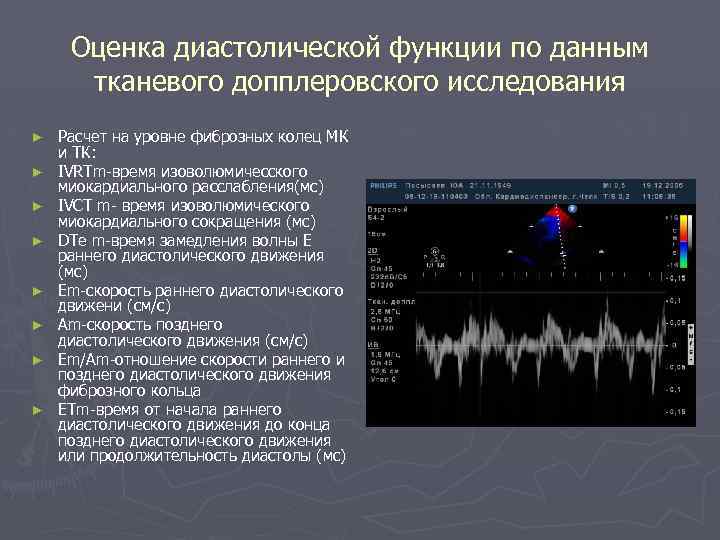

Оценка диастолической функции по данным тканевого допплеровского исследования ► ► ► ► Расчет на уровне фиброзных колец МК и ТК: IVRTm-время изоволюмичесского миокардиального расслабления(мс) IVCT m- время изоволюмического миокардиального сокращения (мс) DTe m-время замедления волны Е раннего диастолического движения (мс) Em-скорость раннего диастолического движени (см/с) Am-скорость позднего диастолического движения (см/с) Em/Am-отношение скорости раннего и позднего диастолического движения фиброзного кольца ETm-время от начала раннего диастолического движения до конца позднего диастолического движения или продолжительность диастолы (мс)

Sm в норме для латерального края 9, 9± 2, 9 см/с ► E' и А‘ в норме для медиального края 10± 1, 3 и 9, 5± 1, 5 см/с ► E' и А‘ в норме для латерального края 12, 0± 2, 8 и 8, 4± 2, 4 см/с ►